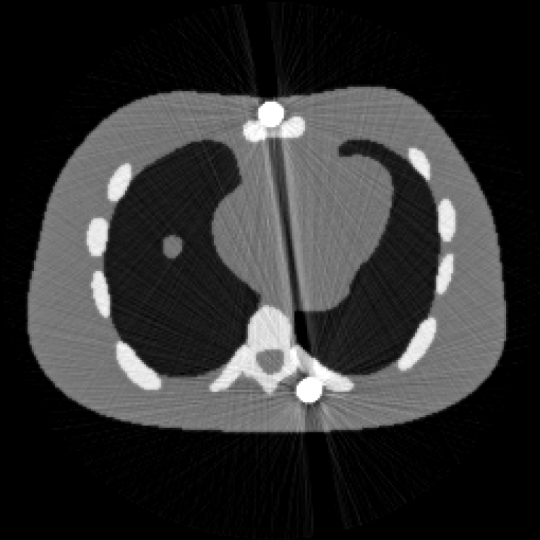

随着医疗技术的进步和新型医用金属材料的不断创新和发展,医疗植入物的需求不断增加,例如骨科植入物、牙科填充物、和冠状动脉支架。但高密度金属假体的存在会使重建的 CT 图像严重退化,导致解剖结构信息丢失,同时伪影的结构可能与某种病灶相似,从而引发误诊等医疗事故。该论文提出一种新的非凸加权变分方法校正金属伪影。不同于常规的使用金属轨迹掩膜的二值化权函数,该方法根据金属伪影在不同区域强度差异,设计了自适应权重,以实现区域性差异化修复从而优化重建效果。进一步采用非凸的

正则化强化边界的对比度,引入图像的有界性约束进一步提升重建精度。基于全变差的预对偶形式,设计了两类有效且全局收敛的一阶原对偶算法求解上述非凸模型。大量数值实验结果验证了该方法的有效性(图1,图2),特别在预分割不准确的情况下,所提出的算法的重建精度得到显著提升。此外,所提出的全分裂算法比当前最具代表性的重加权JSR算法相比,计算速度平均提升两倍。

图1 含金属伪影的 NCAT图像 图2 校正后的NCAT 图像